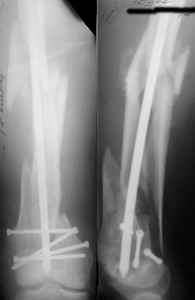

A new toy is more interesting and fashionable. And anyway it is not panacea, i have already seen presentations with LISS failures like the attached one presented by D.Seligson. And people also demonstrated incisions say that the method is not so LESS invasive as it supposed to be.

I presented a series of ~25 such cases at EuroTrauma'2004. Many cases were discussed here. I attach am example. Look also recent cases at http://www.hwbf.org/hwb/conf/alex58/scfx.htm,

http://www.hwbf.org/hwb/conf/alex63/alex63.htm

At that moment we had in stock only the 10 mm solid nails so of course there was no idea about early weight bearing. But it was quite enough for early knee ROM excersises (see attached). Two locking screws through the distal block provided that.